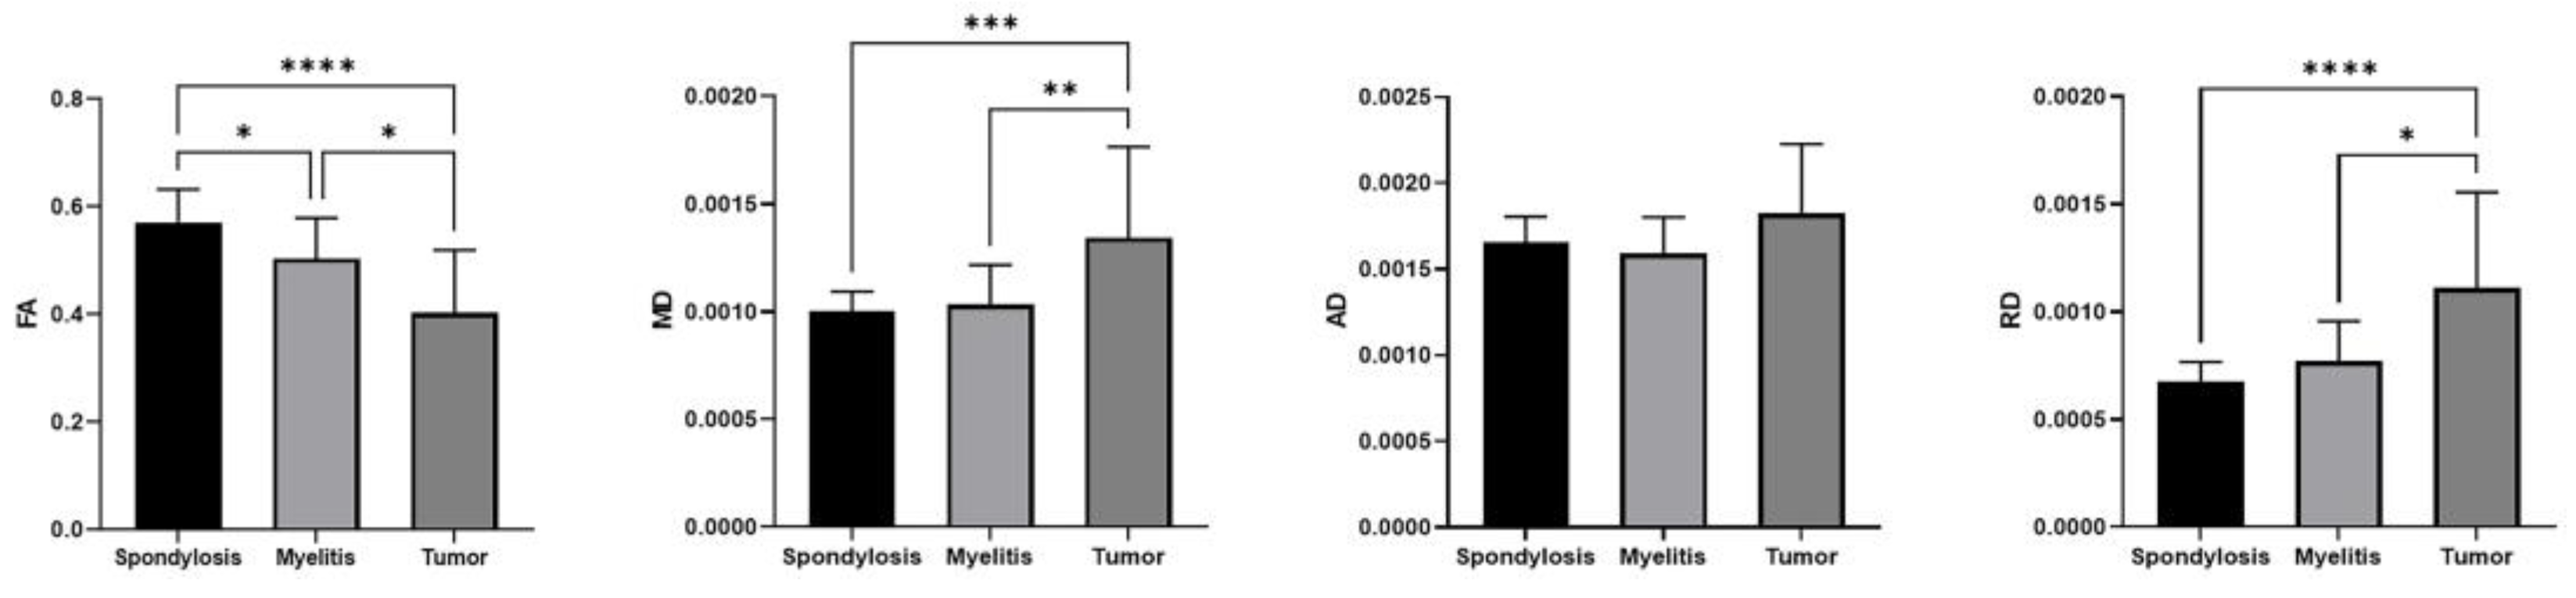

3.2. DTI Indicators in Spondylosis, Myelitis, and Spinal Tumors

3.3. Discriminative Power of DTI Indicators in Spinal Pathologies